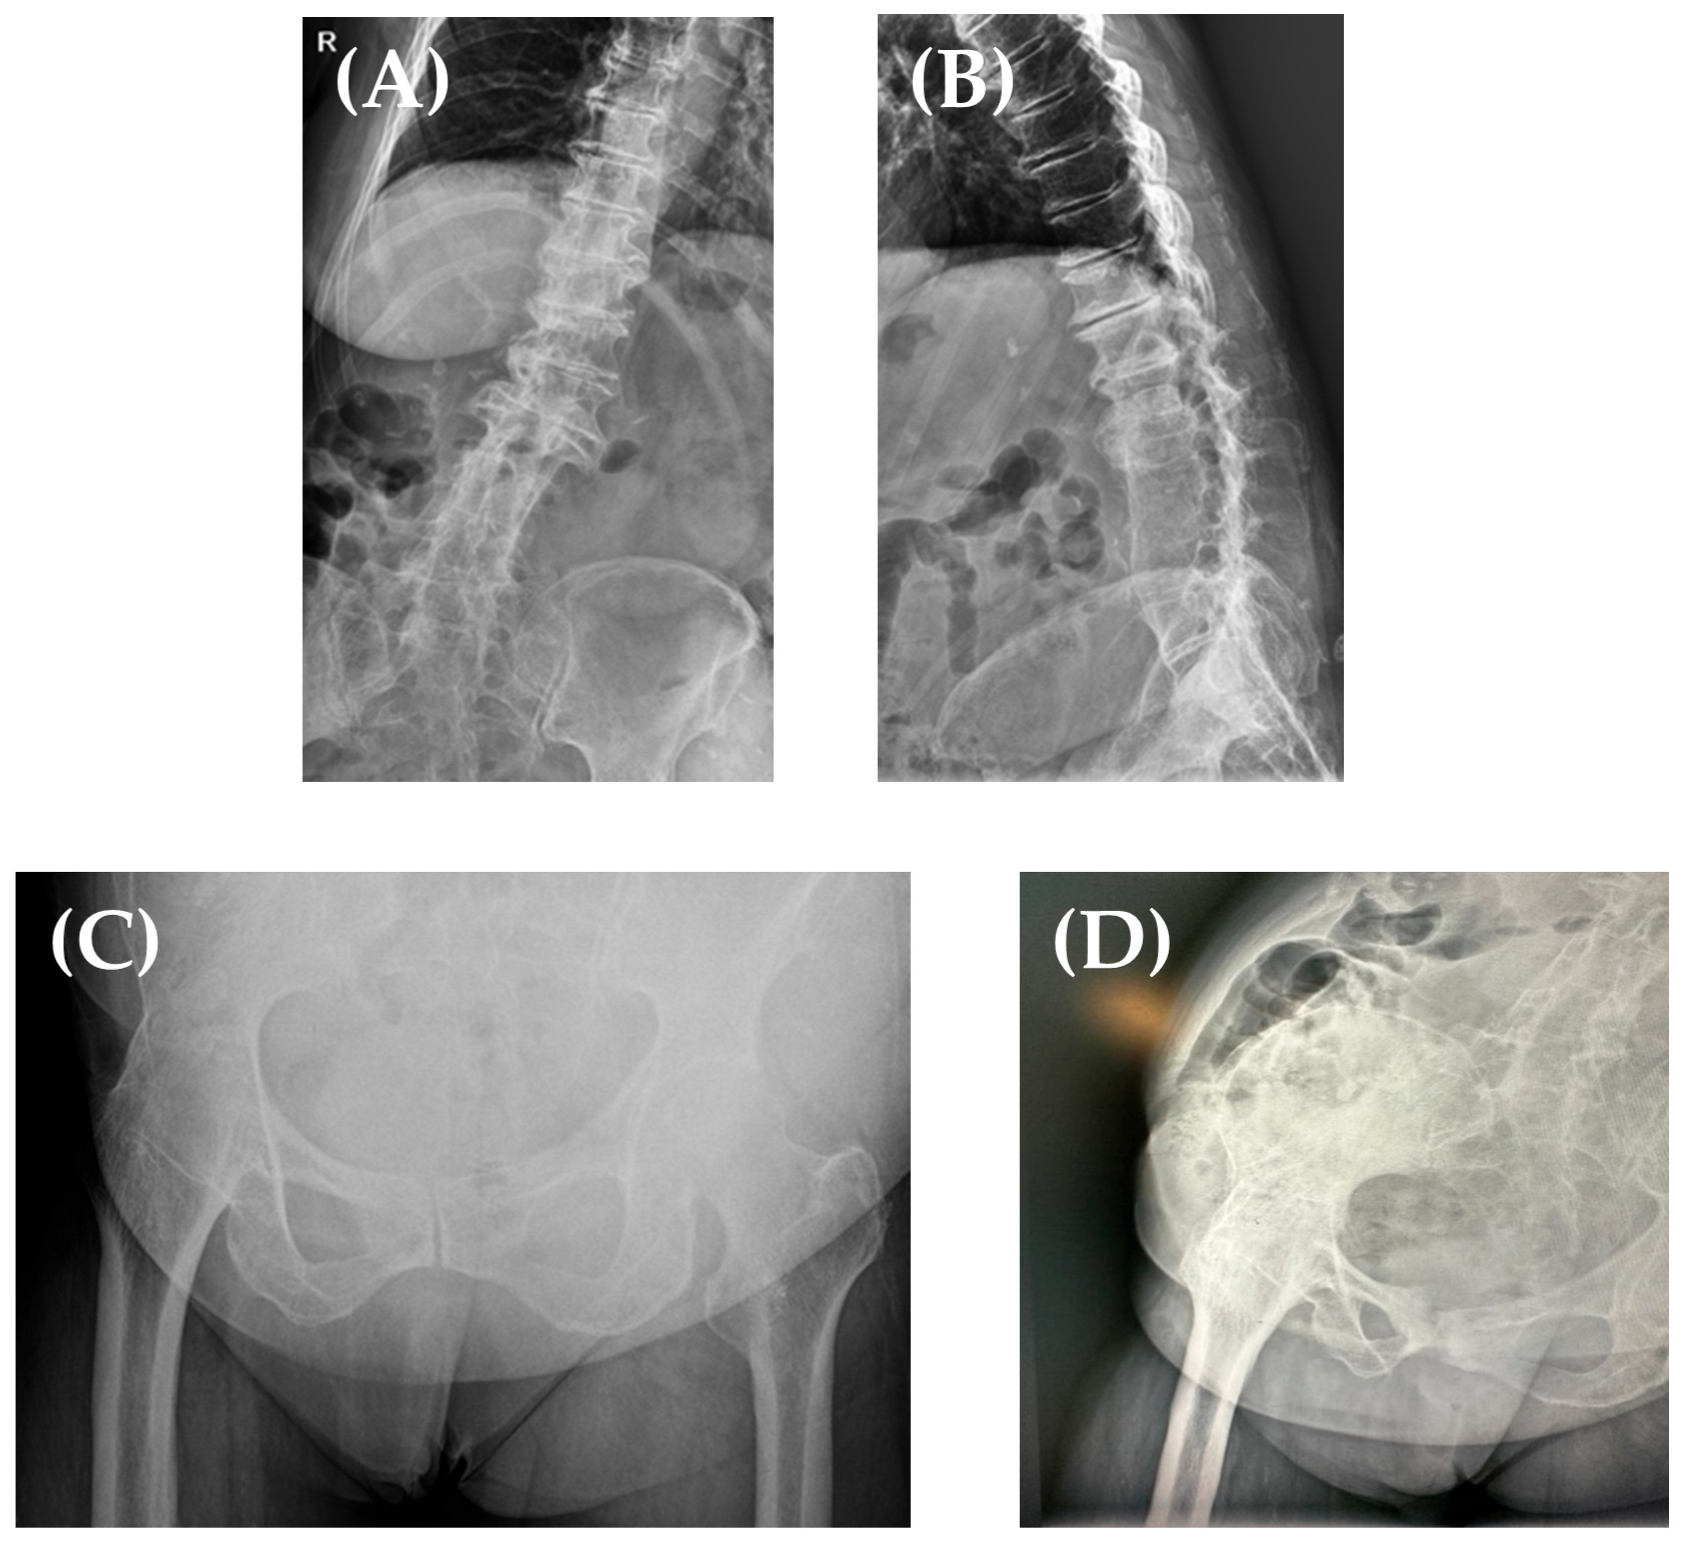

Her X-ray findings (Figure 2) were the following: stage IV Kelgreen and Lawrence right knee osteoarthritis; her right hip was ankylosed in 15° of flexion, neutral abduction/adduction, and internal/external rotation; in addition, she had a thoracolumbar kyphoscoliosis, with L2–L4 vertebral block and severe degenerative changes.

Figure 2. Thoracolumbar kyphoscoliosis, with L2–L4 vertebral block (A,B). Right hip fused in 15° of hip flexion, neutral hip abduction/adduction, and neutral hip internal/external rotation (AP view—C, Lateral view—D).